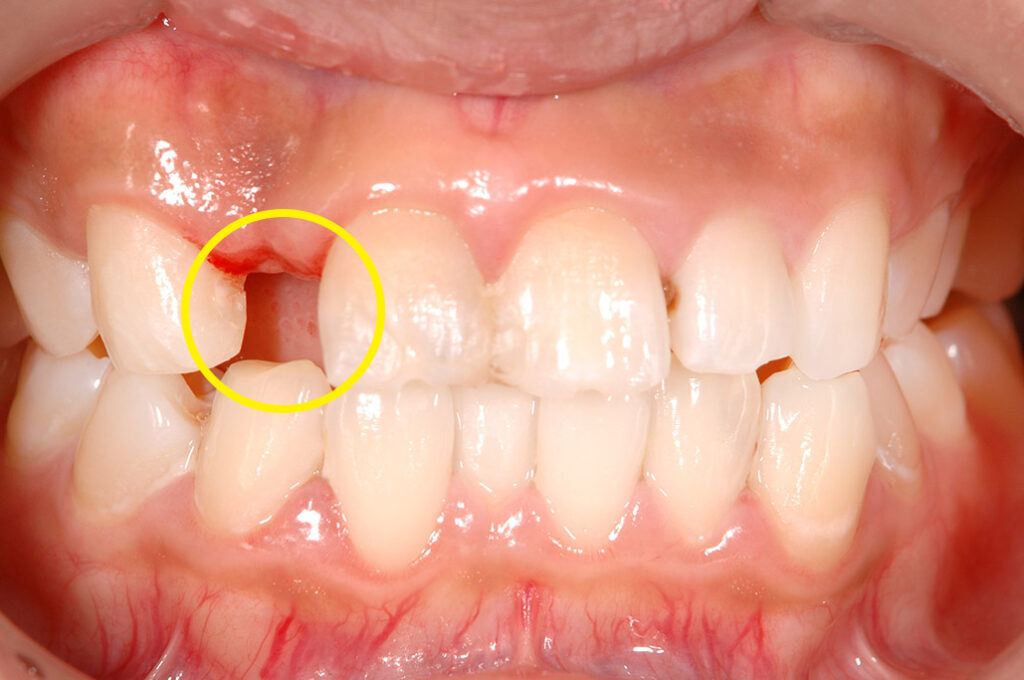

交通事故による前歯の欠損を復元した患者さまの症例です。